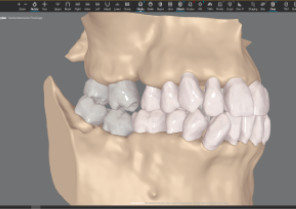

Auto-generates a 3D model with roots, crown, and bone for more-informed treatment planning.

See patients' roots, crowns, and bone in one auto-generated 3D model with new CBCT integration.

Maximizes the efficiency of powerful ClinCheck tools like 3D Controls.

Shows you real root renderings and bone visualizations based on actual scan data.

Simulates root movement along with tooth movement.

Roots with semitransparent bone

Roots with semitransparent bone